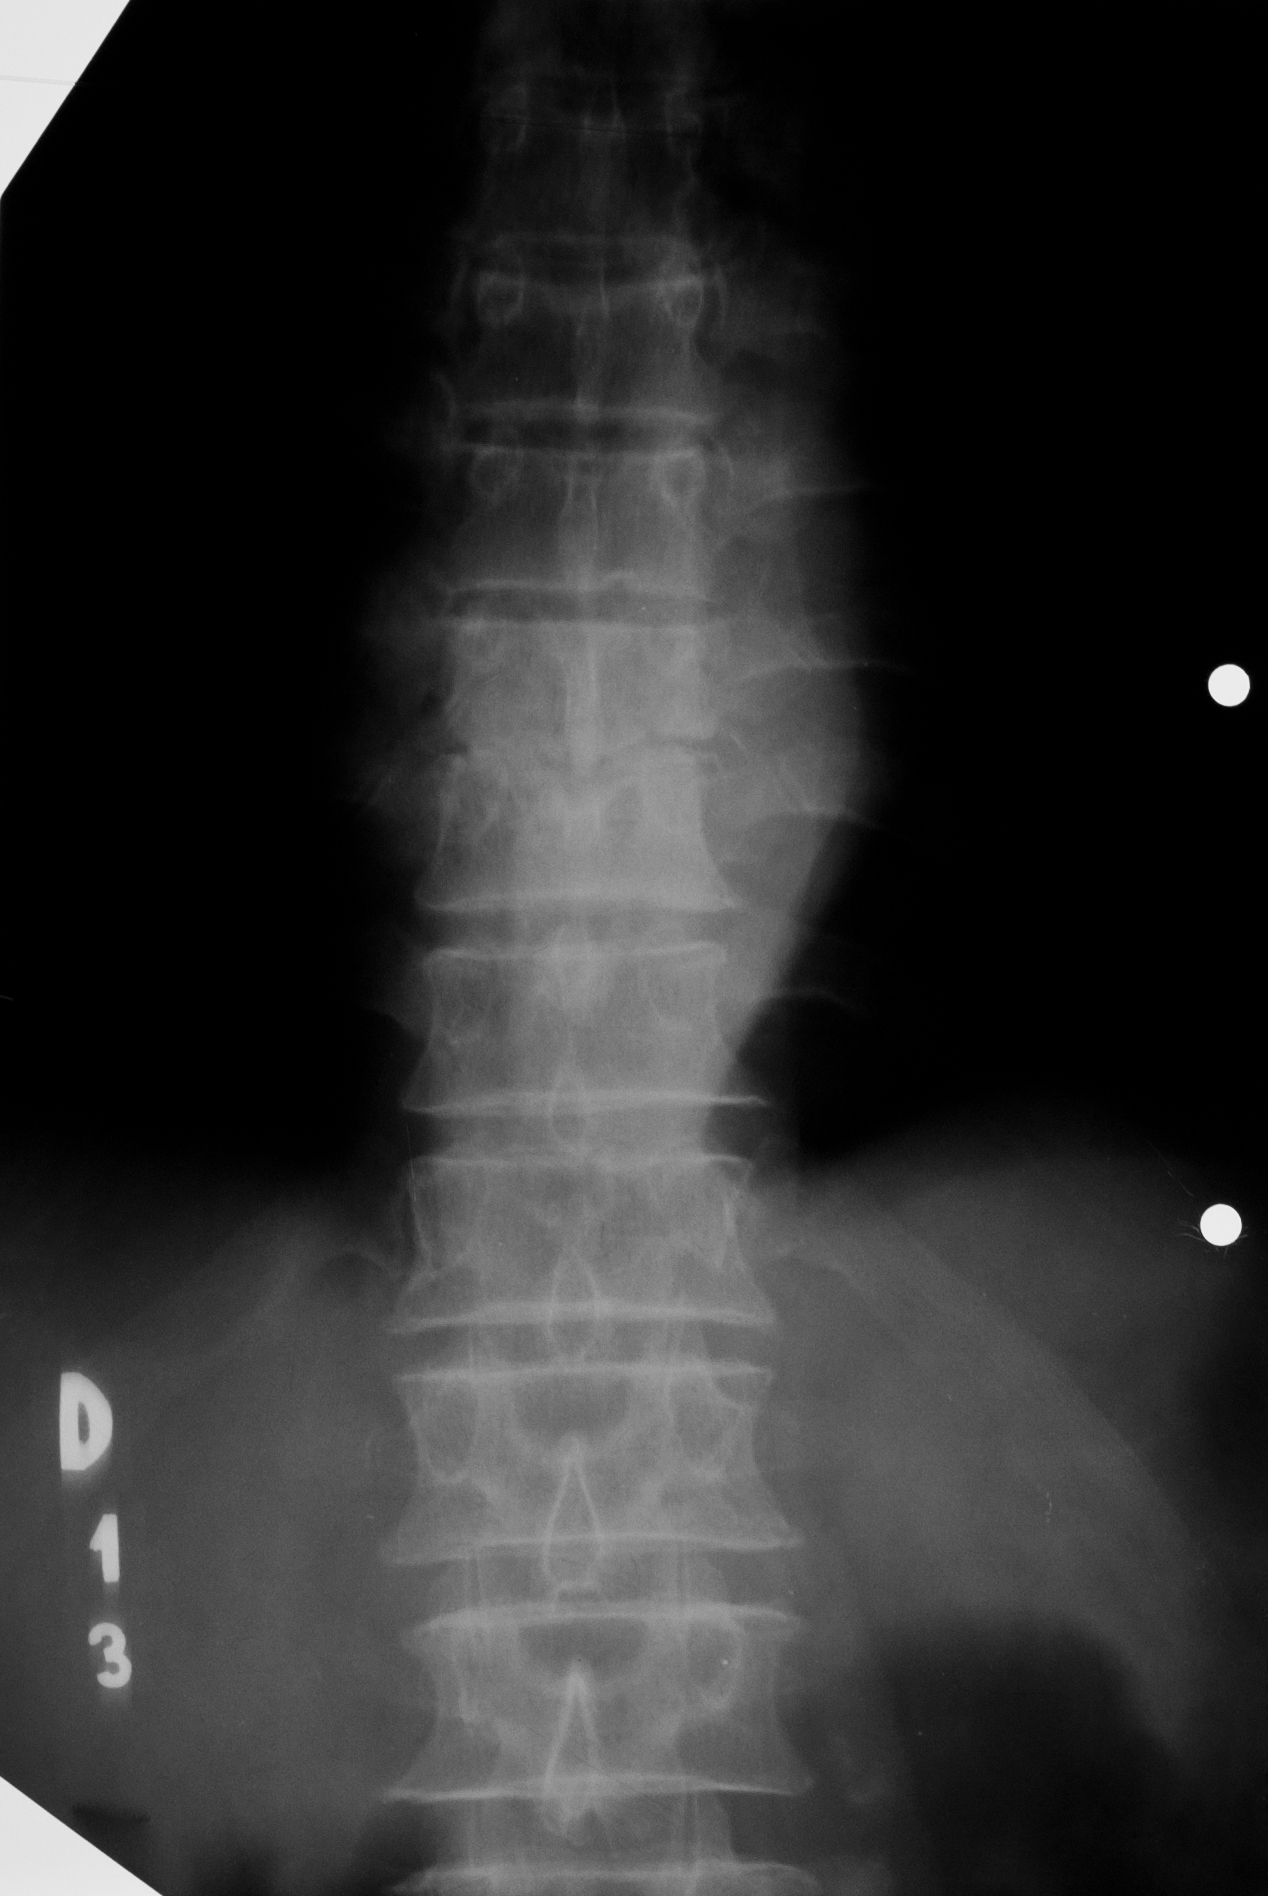

Cifoza rotunda, caracteristica persoanelor in varsta, datorata osteoporozei generalizate

- radiografie de coloana toracala, cu accentuarea cifozei toracale

- corpuri vertebrale mai putin opace decat ar trebui si avand forma trapezoidala, nu dreptunghiulara, cu tasare anterioara a acestor corpuri vertebrale